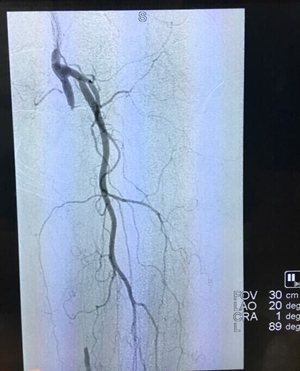

手术后影像图: